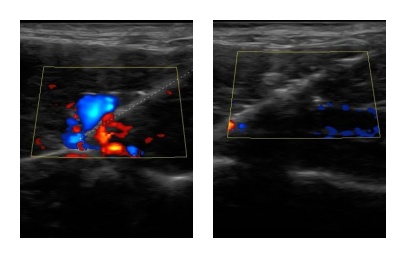

肿瘤微创介入治疗已是人医常规治疗方案之一,其在宠物肿瘤医学近年亦越来越受关注,越来越多医师开始学习这项技术造福宠物们。下图是恩诺的热消融在彩超导引介入烧灼肝脏前后的变化图,左图烧灼前可以看到肝脏有非常丰富的血流,右图烧灼后可以看到肝脏血液几乎局部烧干竭了,达到热消融预设的临床效果;正符合热消融临床指南「烧干净」把肿瘤细胞烧干净、把肿瘤内血液烧干净!